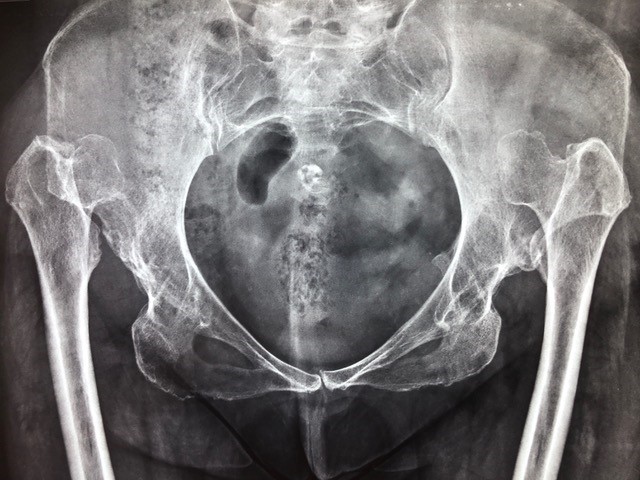

Όταν το εξάρθρημα δεν έχει διαγνωστεί ή δεν έχει αντιμετωπιστεί με επιτυχία στην βρεφική ή παιδική ηλικία, μπορεί να οδηγήσει σε δυσπλασία του ισχίου ή σε ένα μερικώς ή πλήρως εξαρθρωμένο ισχίο κατά την ενήλικη ζωή.

Στον ενήλικα εκδηλώνεται με πόνο, ο οποίος γίνατε εντονότερος όταν εμπλακεί με οστεοαρθρίτιδα. Υπάρχει χωλότητα λόγω αδυναμίας των απαγωγών μυών του ισχίου, βράχυνση του άκρου που μπορεί να φτάσει τα 3-6 εκατοστά η και περισσότερο σπανιότερα.

Παρατηρούνται μεταβολές στην ανατομία του ισχίου και της λεκάνης, οι οποίες αναδεικνύονται με την απλή ακτινογραφία του ισχίου.

Η αξονική τομογραφία δίνει ακριβέστερες πληροφορίες για την διαταραγμένη ανατομία της περιοχής και χρησιμοποιείται στον προεγχειρητικό σχεδιασμό.